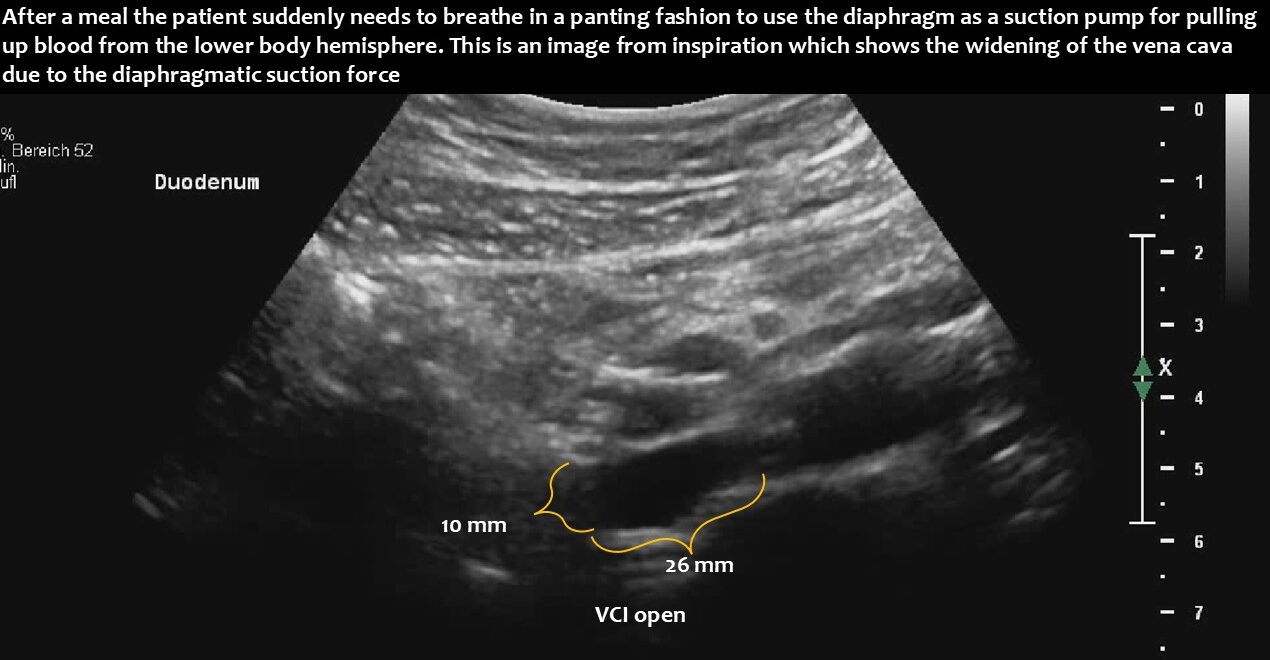

Immediately after food was taken up, the stomach pumped it into the duodenum, which subsequently enlarged and compressed the vena cava.

This suddenly interrupted or massively compromised the venous return from the lower body hemisphere. This led to a sudden drop in the circulating blood volume. Due to reduced lung perfusion as a consequence of the reduction in central flow volume, panting developed to enhance oxygenation of the remaining small blood volume. At the same time, the reduced blood flow to the brain, in combination with hypocapnia as a result of hyperventilation to fight imminent compromise of oxygenation, caused dizziness and a sensation of near fainting.

Functional ultrasound can demonstrate the entire pathophysiological chain, from underlying lordosis to postprandial duodenal enlargement and subsequent vena cava compression, especially when standing after eating.